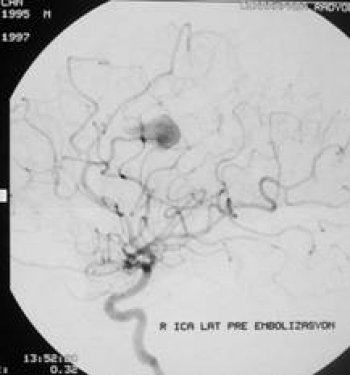

Anevrizma Kliplenmesi

Subaraknoidal boşluğa, arter ya da ven in yırtılması sonucu, kan sızması ile meydana gelen tablo subaraknoidal kanama olarak adlandırılır. Subaraknoidal boşluk veya aralık ise beyinin en dışını saran pia mater adı verilen çok ince zar ile bu tabakanın üzerindeki zar olan arachnoidea arasında kalan mesafedir. Subaraknoidal kanamalar çok değişik nedenlerle meydana gelirse de en sık nedeni anevrizmalardır. Subaraknoidal kanamalar kafa içi patolojiler içinde, birden ölümlere yol açabilen en ağır klinik tabloların başında gelir ve anevrizma rüptürüne bağlı subaraknoidal kanama görülme sıklığı 40 60 yaş grubunda en yüksektir. Anevrizmalı hastaların % 50 sinde, genellikle kanamadan 1 3 hafta önce, uyarıcı belirtiler vardır. Baş ağrısı olguların % 30 unda çoğunlukla anevrizma tarafında olmak üzere tek taraflıdır. Anevrizmal subaraknoidal kanamaların % 30 u uykuda ortaya çıkar. Nedeni bilinmemekle beraber ilkbahar ve sonbahar ayları kanama sıklığının daha fazla görüldüğü aylardır.